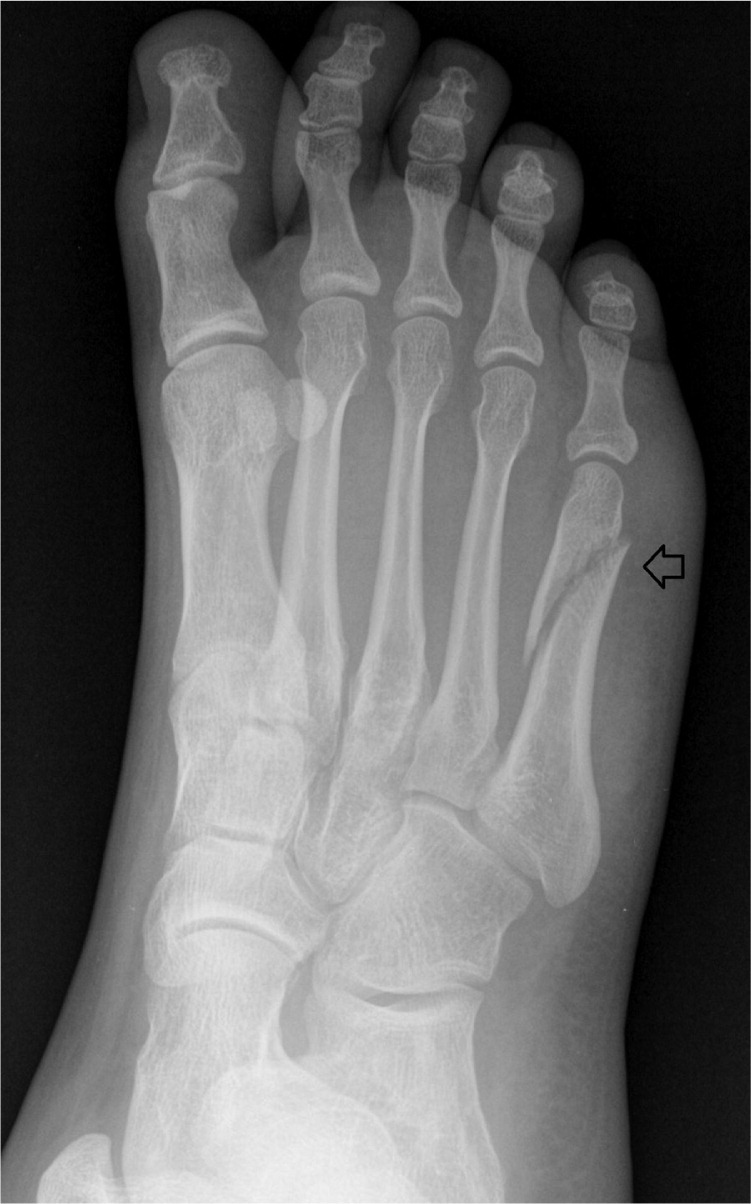

기타 골절 수술

5th metatarsal bone fracture

phalanges fracture

- 특히 허리 디스크로 발목거상이 안되는 환자가 무리하게 걸으면 발생하는 경우 있음.